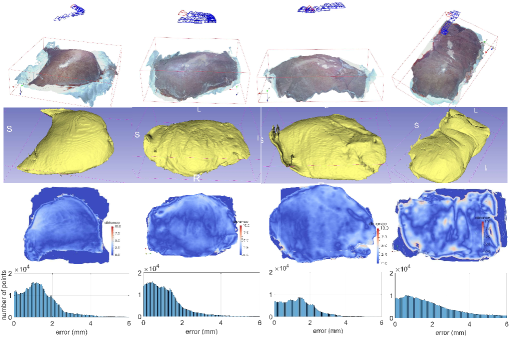

In order to evaluate the quantified accuracy of our 3D reconstruction method, we used the CT imaging of tissues as the gold standard. In this experiment, CT scans of four ex-vivo porcine livers and three kidneys were obtained (Siemens Somatom, Erlangen Germany) with a 0.6 mm resolution at our hospital, and we used the 3D Slicer software to segment the tissue models from the CT images, as shown in Fig. 9. We captured stereo videos of the tissues with the KARL-STORZ stereo laparoscope, the details of which are in Tab. II. Surfaces of livers and kidneys are very smooth and have low textures, but the proposed method was still able to reconstruct the 3D models, as shown in Fig. 7. To quantify accuracy, we registered the 3D reconstructed model with the CT segmentation results by first manually selecting landmarks, such as tissue tips, edge points and other recognizable points, and then refining the registration with the ICP algorithm. As shown in Fig. 7 (a), the root mean square errors (RMSE) with the liver cases are 1.3, 1.1, 1.4 and 2.0 mm respectively. The fourth liver case has a relatively larger error because we used an entire piece of liver and the video was captured at a larger camera-tissue distance. The results on porcine kidneys are shown in Fig. 7 (b), the RMSE of which are 1.0, 1.0 and 1.1 mm respectively. The histograms of errors are also provided in Fig. 7, which show that most points have an error of less than 2mm. It is worth noting that there are multiple sources of errors, including 3D reconstruction error, CT resolution error, CT segmentation error and registration error that contribute to the obtained RMSE in this experiment. In addition, because the livers and kidneys were placed on a textureless plastic sheet and part of the sheet were also included in the 3D reconstructed model, which is difficult to be totally removed (see the tissue edges in the distance maps of Fig. 7), so the quantified error may also include a small amount of the background. Therefore, it is a reasonable assumption that the actual error of our 3D reconstruction method is smaller than the reported RMSE.